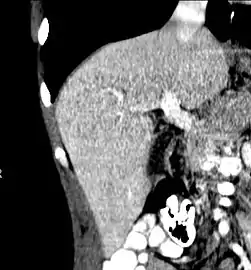

With the recent advances of noninvasive imaging, living liver donors usually have to undergo imaging examinations for liver anatomy to decide if the anatomy is feasible for donation. The evaluation is usually performed by multidetector row computed tomography (MDCT) and magnetic resonance imaging (MRI). MDCT is good in vascular anatomy and volumetry. MRI is used for biliary tree anatomy. Donors with very unusual vascular anatomy, which makes them unsuitable for donation, could be screened out to avoid unnecessary operations.

MDCT image. Arterial anatomy contraindicated for liver donation

MDCT image. Portal venous anatomy contraindicated for liver donation

MDCT image. 3D image created by MDCT can clearly visualize the liver, measure the liver volume, and plan the dissection plane to facilitate the liver transplantation procedure.

Phase contrast CT image. Contrast is perfusing the right liver but not the left due to a left portal vein thrombus.